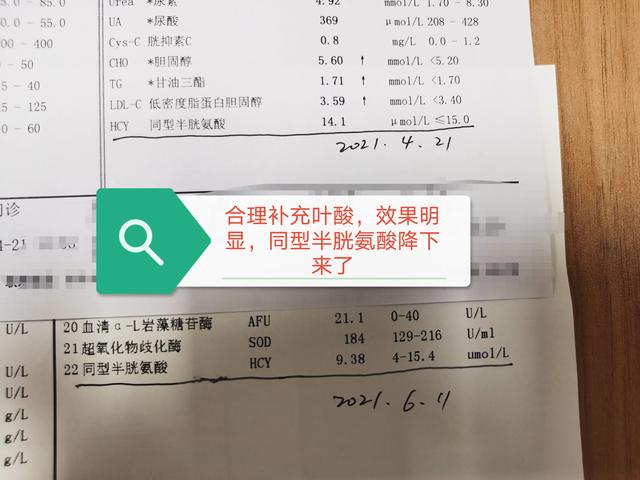

Élévation de la 3-homocystéine

Les patients chinois atteints d'infarctus cérébral en milieu rural, en plus des patients souffrant d'hypertension artérielle, ont une autre raison importante : il y a trop d'hypertension artérielle de type h, c'est-à-dire accompagnée d'une élévation de l'homocystéine chez les patients souffrant d'hypertension artérielle. Ce type d'hypertension représente le plus grand danger d'infarctus cérébral. C'est pourquoi, en Chine, même si la tension artérielle est normale, l'infarctus cérébral est une raison importante.

À ce propos, certains diront que les directives américaines en matière d'accidents vasculaires cérébraux ne recommandent plus la prise de suppléments d'acide folique, et que les Chinois doivent donc continuer à prendre des suppléments d'acide folique. Les Américains ne présentent généralement pas de carence en acide folique à l'heure actuelle, de sorte que leurs lignes directrices ne recommandent plus la supplémentation en acide folique, mais la Chine est différente, de nombreuses personnes en Chine présentent aujourd'hui de faibles taux sériques d'acide folique, de sorte que davantage de personnes doivent se supplémenter en acide folique. La supplémentation en acide folique peut prévenir efficacement l'apparition et le développement de l'infarctus cérébral, et c'est là que réside le plus grand avantage de la supplémentation en acide folique.

- Supplémentation modérée en vitamine B6, vitamine B12, acide folique et autres nutriments pour réduire la concentration d'homocystéine dans le sang.